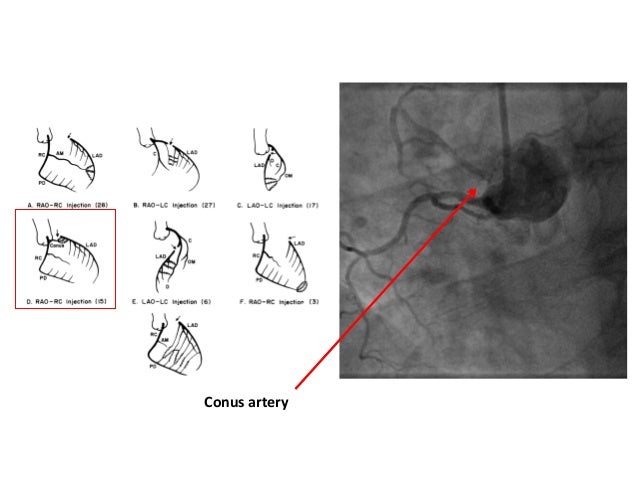

Technique ping pong. Join the PingPong World now to meet up with other table tennis enthusiasts from around the globe Learn a thing or two about the game of PingPong and help teach others how to become more efficient with their paddles Checklist for new members /forum/ Introduce yourself Ask questions in the /forum/ Forum Share some /inspiration/ Inspiration. Perforation of a left internal mammary artery (LIMA) graft during percutaneous coronary intervention is a rare event We report a case of midLIMA perforation treated by a polytetrafluoroethylenecovered stent using a modification of the dual catheter ("ping pong") technique We propose that use of this modification when possible will further improve safety of treating a perforation. The “shakehand” paddle grip is the typical European style of holding a ping pong paddle Under this hold, the head of the paddle points upward, and the appearance of your hand is similar to shaking someone’s hand A person who is holding the shakehand grip is holding the blade of the paddle with the use of his/ her thumb and index finger.

To Ping Pong forehand, do follow the following steps Place your feet properly, with the right foot (for righthanded people) slightly behind This gives a proper impulse Place the racket between the hip and the shoulder Stand at the center of the table Once the ball hits your side of the. The technique of using two different catheters into the same coronary artery, the socalled “pingpong” technique, is a technique described for treating complications during percutaneous coronary intervention (PCI), like perforations or rotational atherectomy burr entrapment. 1 Forehand Drive Technique The first fundamental table tennis skill that you should learn is the feeling of the ballDriving skills helps you quickly get this feeling Unlike many basic table tennis lessons, who propose you to learn the “grip” or the “stance” first.

“Ping‐pong” guide catheter technique for retrograde intervention of a chronic total occlusion through an ipsilateral collateral † Emmanouil S Brilakis MD, PhD, FSCAI Corresponding Author. A competitive ping pong player is able to consistently send this type of serve while beginners and intermediate players can only pull it off every once in a while Following our techniques, we’ll teach you how you can finally challenge even the best ping pong player in the house and win. Forehand Technique in Ping Pong – Basic Technique Beginners Should Know 2 Backhand drive This is a key shot that shows the basics of a topspin made using a backhand The backhand drive is not very much powerful but can be effective if used with speed and precision This drive helps you block any kind of a shot and is very useful in making.

Abstract Perforation of a left internal mammary artery (LIMA) graft during percutaneous coronary intervention is a rare event We report a case of midLIMA perforation treated by a polytetrafluoroethylenecovered stent using a modification of the dual catheter ("ping pong") technique We propose that use of this modification when possible will further improve safety of treating a perforation. It is ideal to have both types of strokes in your arsenal The best ping pong players play a mixture of both strokes in every game they play There are many different types of ping pong strokes that one can play however some of them are given below;.